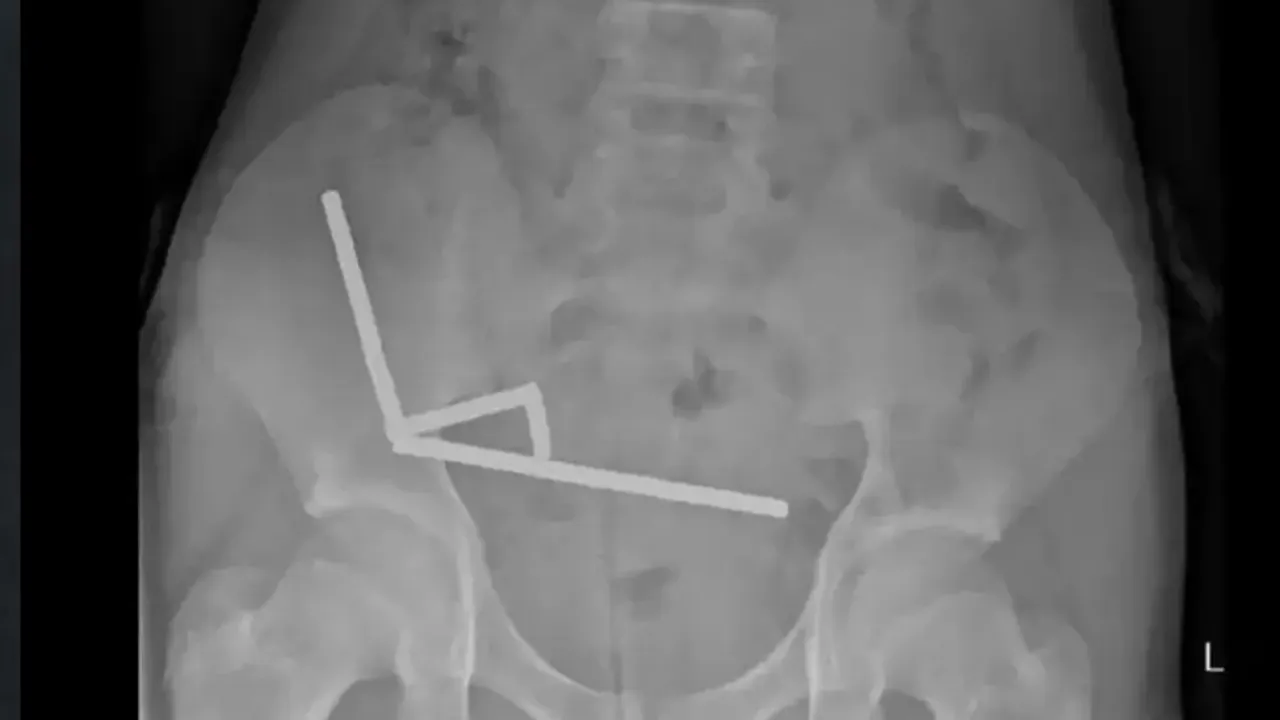

Çocuğun, “yaklaşık bir hafta önce 5x2 milimetre büyüklüğündeki güçlü neodim mıknatıslardan 80 ila 100 tanesini yuttuğu” belirtildi. Ancak neden böyle bir girişimde bulunduğu açıklanmadı.

Doktorlar, yutulan mıknatısların bağırsaklarda bir araya gelerek baskı oluşturduğunu; bunun da ince ve kalın bağırsağın dört bölümünde doku ölümüne yol açtığını açıkladı. Ameliyatta hem mıknatıslar hem de ölü dokular başarıyla çıkarıldı. Çocuk, operasyonun ardından sekiz gün boyunca hastanede tedavi gördü.